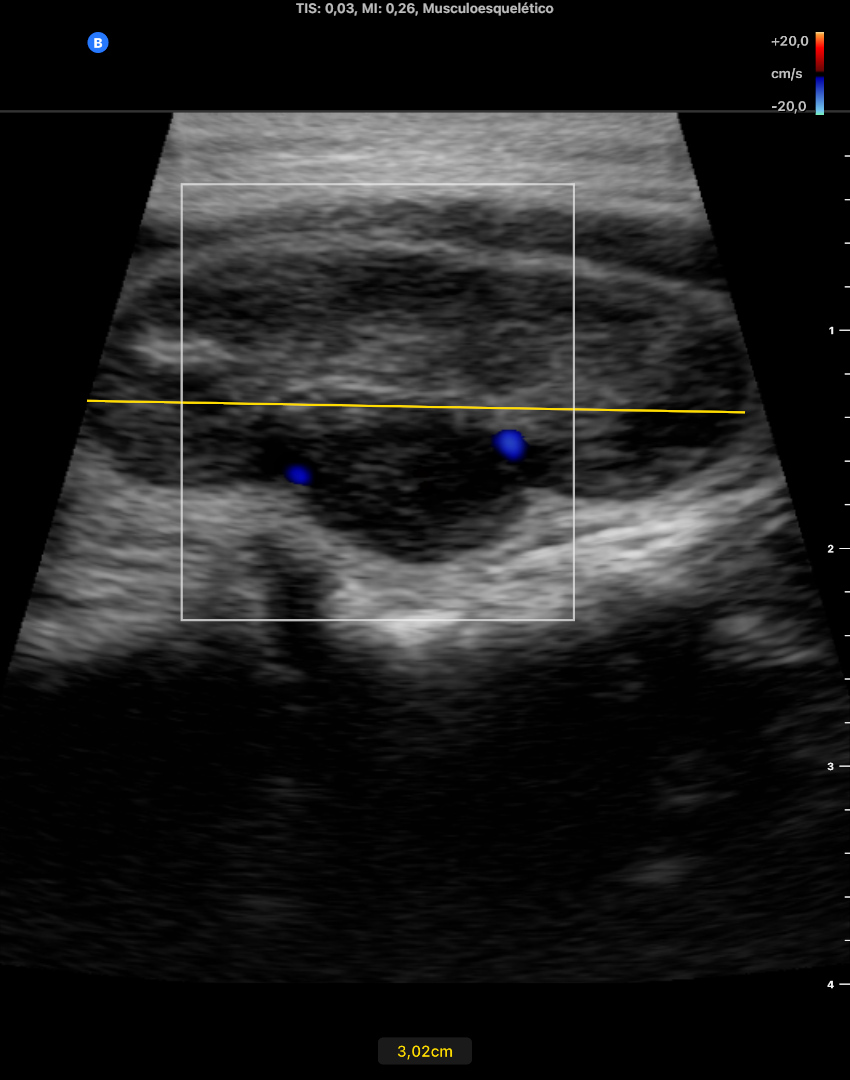

En LTI se objetiva un nódulo predominante de 30 mm de diámetro L y 16 x 14 mm en diámetros APxT captante de Doppler, de contenido casi solido, TIRADS 4-5. No adenopatias laterocervicales sospechosas.

Nódulo tiroideo TIRADs 5 en LTI, recomendándose obtención de muestras para AP ecoguiada.